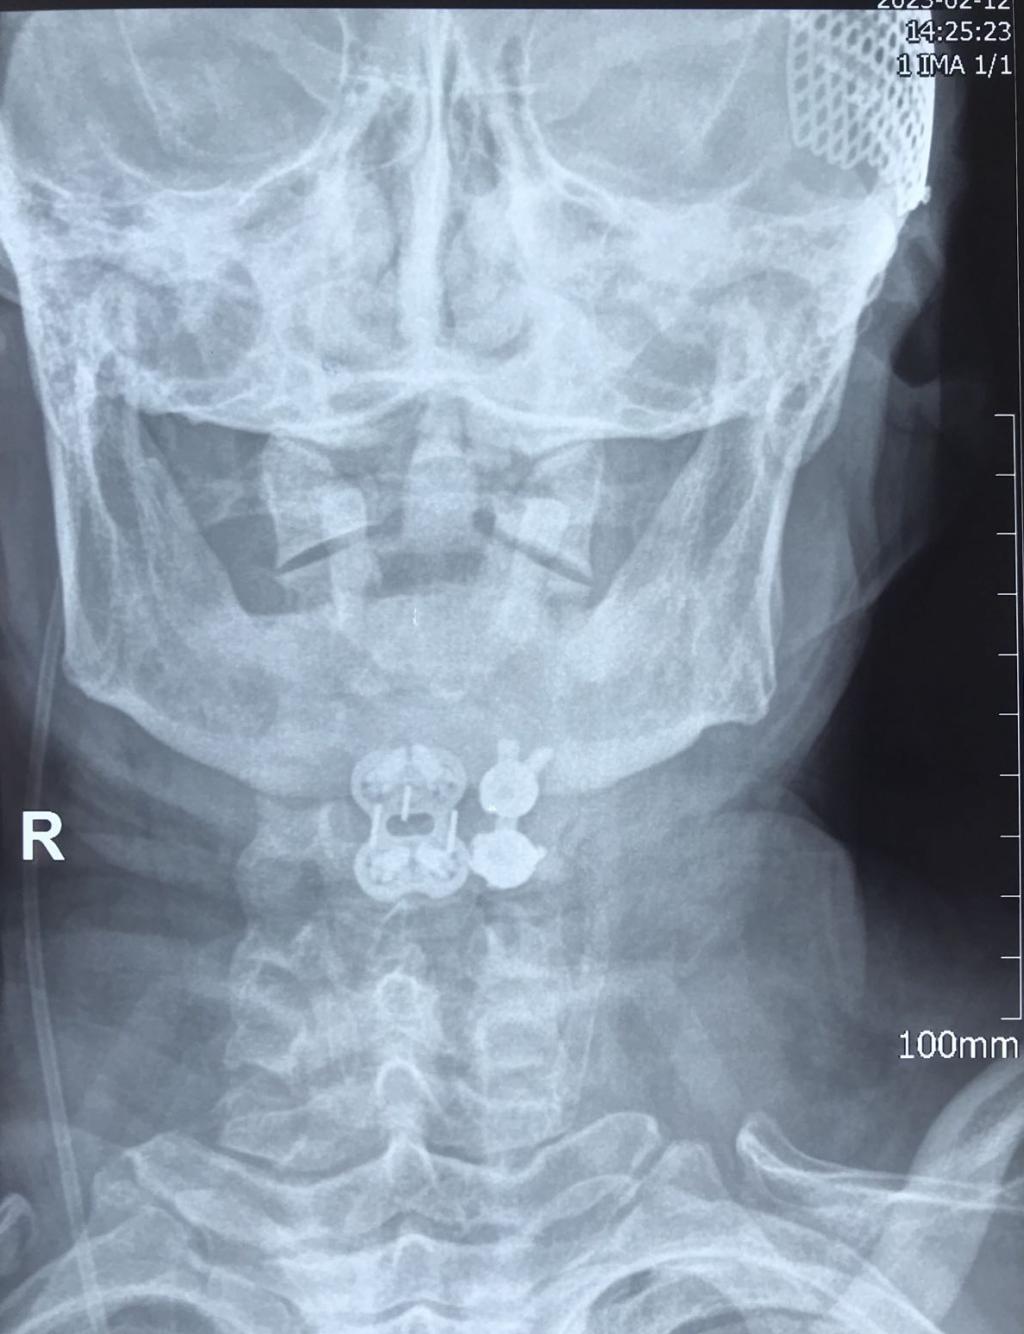

近日,一位颈部外伤合并肢体瘫痪症状患者来到乐鱼在线登录入口骨一科就诊。经入院后紧急检查,发现患者为颈3.4椎体骨折、脱位,并有右后侧关节突关节骨折、绞索,四肢肌力约3级。

入院后,科室立即进行常规术前检查,给予8公斤大重量颈枕带牵引,但因关节脱位的绞索,颈椎复位困难。几日后,患者在牵引过程中出现右上肢抽痛加重,肌力减低表现。紧急时刻,骨一科决定立即为患者行急诊手术治疗。

经过有序准备,为患者先行颈后路减压,解锁关节突绞索,牵引复位,使用颈椎侧块螺钉固定,同时椎板间植骨融合。随后再将患者转为仰卧位,再行颈前路脱位椎体的间盘摘除,融合器植入,钢板螺钉固定,历时3小时,顺利结束。患者术后恢复良好,肢体功能状态较术前改善显著,上肢抽痛症状消失,肌力已达4-5级,患者及家属对治疗效果颇为满意。